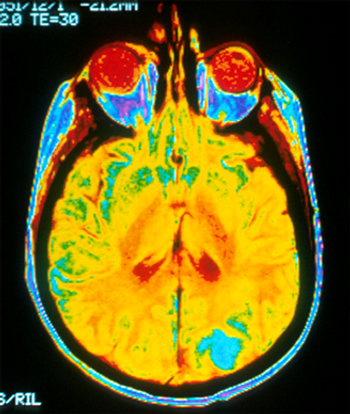

After adjusting for traditional vascular risk factors, radiologists encourage aggressive monitoring of COVID-19 patients for blood flow changes to the brain.

When used together, non-contrast simple CT and CT perfusion have higher prediction rates

Edema visualization improves detection of early infarcts.